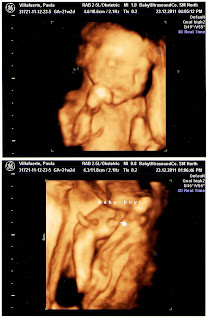

At 22 Weeks, taken December 23 on my husband's birthday. Discovered the gender.

I have no idea what's going on in these pictures,

supposedly we are to see the eyes, nose and then the lips.

24 Weeks.